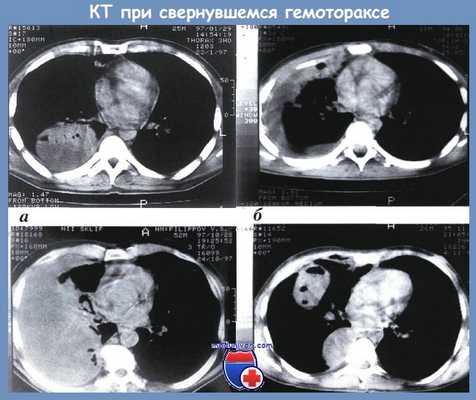

Формы свернувшегося гемоторакса по данным КТ:

а — локальный; б — плащевидный; в — тотальный; г — фрагментарный

Спиральная компьютерная томография дает наиболее исчерпывающую информацию о возникновении и развитии стадий свернувшегося гемоторакса. КТ-признаки свернувшегося гемоторакса представляют собой сочетание объективных качественных и количественных характеристик: наличие патологического содержимого, его точный объем, локализация, форма, контуры, структура (плотность, однородность), соотношение плотной и жидкостной фракций, их смещаемость. Чувствительность метода в наших наблюдениях составила 100 %. В отличие от УЗИ и МРТ, этому исследованию не препятствовало наличие эмфиземы мягких тканей, повязок, металлических конструкций и инородных тел. У больных в тяжелом состоянии в ходе КТ продолжалась инфузионно-трансфузионная терапия и ИВЛ. Противопоказаниями к КТ были нестабильная гемодинамика и масса тела свыше 100 кг.

На основании изучения результатов КТ с клинической точки зрения выделены 4 формы свернувшегося гемоторакса [Абакумов A.M.]: локальный, когда свертки крови расположены в синусах плевральной полости (чаще всего заднем), над диафрагмой, паракостально, паравертебрально, парамедиастинально и в междолевой борозде (рис. а); плащевидный, когда свертки крови располагаются одним блоком, узкой полосой, занимают синусы, паракостально и паравертебрально (рис. б); тотальный — свернувшийся гемоторакс объемом свыше 1500 см3 занимает одним блоком большую часть плевральной полости (рис. в); фрагментарный, когда имеются не связанные друг с другом, отграниченные скопления свертков крови в различных отделах плевральной полости и, как показывает опыт, в различных стадиях организации (рис. г).